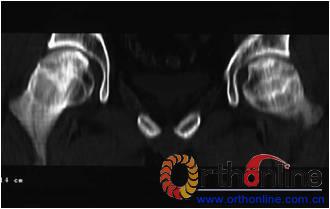

图3-2 女,30岁,SARS患者骨坏死,(1)术前MRI示双侧骨坏死;右Ⅱc期C3型,左Ⅱb期B型,打压植骨术(加BMP2),(2)5年后CT显示病灶修复好,关节功能优